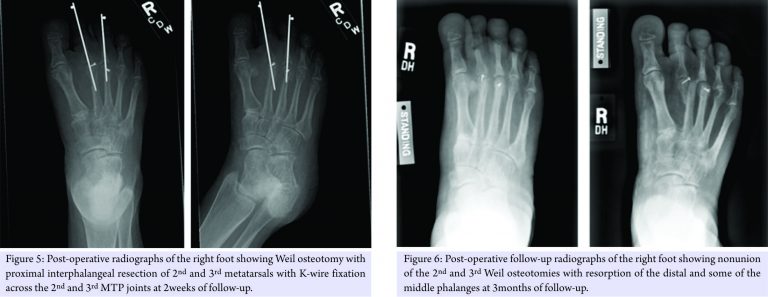

Following 7-week post-operative recovery period from the left foot surgery, the patient underwent Morton’s neuroma excision and Weil osteotomy with second and third PIP resection and K-wire fixation in the right foot (Fig. 5). Extensor tendon lengthening was also performed in the same foot. Post-operative course was complicated by atrophic nonunion of the osteotomies (Fig. 6), as well as worsening of her neuropathic pain.

HCS is a rare autosomal dominant disorder characterized principally by acroosteolysis (dissolution) of the distal phalanges with possible associated digit abnormalities, distinctive craniofacial and skull features, dental anomalies, and proportionate short stature. While dysmorphic features at birth and presence of acroosteolysis allow diagnosis early in life, the full phenotype is rarely present in childhood. Instead, the various clinical and radiologic abnormalities manifest at different ages and often progress with time [1,3]. Treatment of this disorder is generally symptomatic and the prognosis is quite good. Morbidity is mostly related to bone changes secondary to acroosteolysis as well as basilar invagination resulting in neurological complications. Presentation and management of toe and foot deformities in patients with HCS are not well described in the literature. Although previous reports have described the management of other manifestations of HCS [6,7,13,14], we were unable to find any specifically addressing management of foot deformities in these patients. Acroosteolysis and underlying collagen abnormalities intrinsic to HCS predispose these patients to the poor post-operative bone and soft tissue healing. There are few reports describing orthopedic challenges and complications associated with operative management in these patients [15,16]. Anecdotally, any surgical intervention done for bony and joint deformities may thus have a higher complication rate of nonunion and recurrence. Our patient was noted at 5-week post-operative follow-up to have a recurrence of the deformity of the left second MTP joint after removal of K-wire fixation. Failure of symptomatic relief may be affected by progressive neuropathy [17], which was also observed in our patient. As such, any bony or soft tissue surgical intervention should be sought with caution and consideration of these post-operative complications.